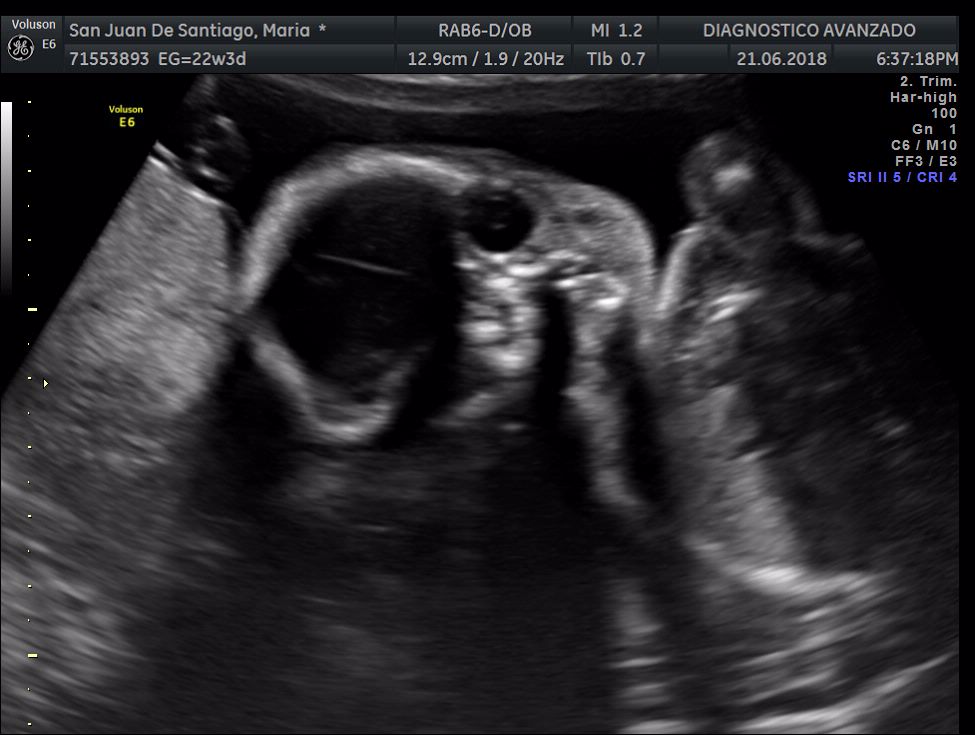

¡Hola a todos! Hoy hemos ido a hacer la tradicional ecografía 3D de la niña, os dejamos todo el material (aunque es un poco demasiado).